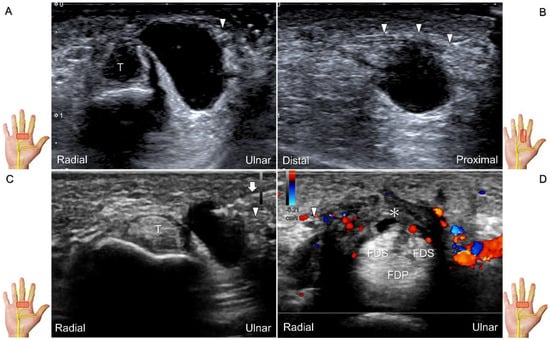

The transducer can be placed in the axial plane on the distal one-third of the forearm with the forearm supinated. The median nerve travels between the flexor digitorum superficialis and flexor digitorum profundus muscles. It gradually runs superficially to enter the carpal tunnel. The carpal tunnel inlet is defined as the plane crossing the scaphoid and pisiform (Figure 2A), whereas the plane linking the trapezium and hook of the hamate serves as the carpal tunnel outlet (Figure 2B).

Clinical Implication

Carpal tunnel syndrome is the most common entrapment neuropathy whereby the median nerve is entrapped by various causes, like hypertrophy of the flexor retinaculum (Figure 2C,D) and compression from the accessory muscles, swollen tendons, ganglions, and bony fractures within the tunnel. Ultrasonographic changes encompass swelling proximal to the entrapment site (Figure 3A), flattening over the entrapment site (Figure 3B), intraneural hypervascularity (Figure 3C), and focal loss of the trimline pattern (Figure 3D).

Figure 2. Sonographic/normal imaging of the median nerve from the inlet (A) to the outlet (B) of the carpal tunnel. Hypertrophy of the flexor retinaculum at both the inlet (C) and outlet (D) of the carpal tunnel. Asterisk: median nerve; small white arrowheads: normal flexor retinaculum; large arrowheads: hypertrophy of the flexor retinaculum. FCR: flexor carpi radialis; S: scaphoid; P: pisiform; T: trapezium; H: hook of the hamate.